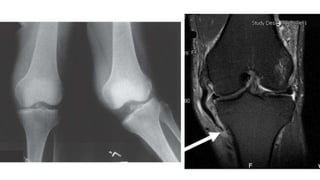

MRI

POSTERIOR SAG SIGN